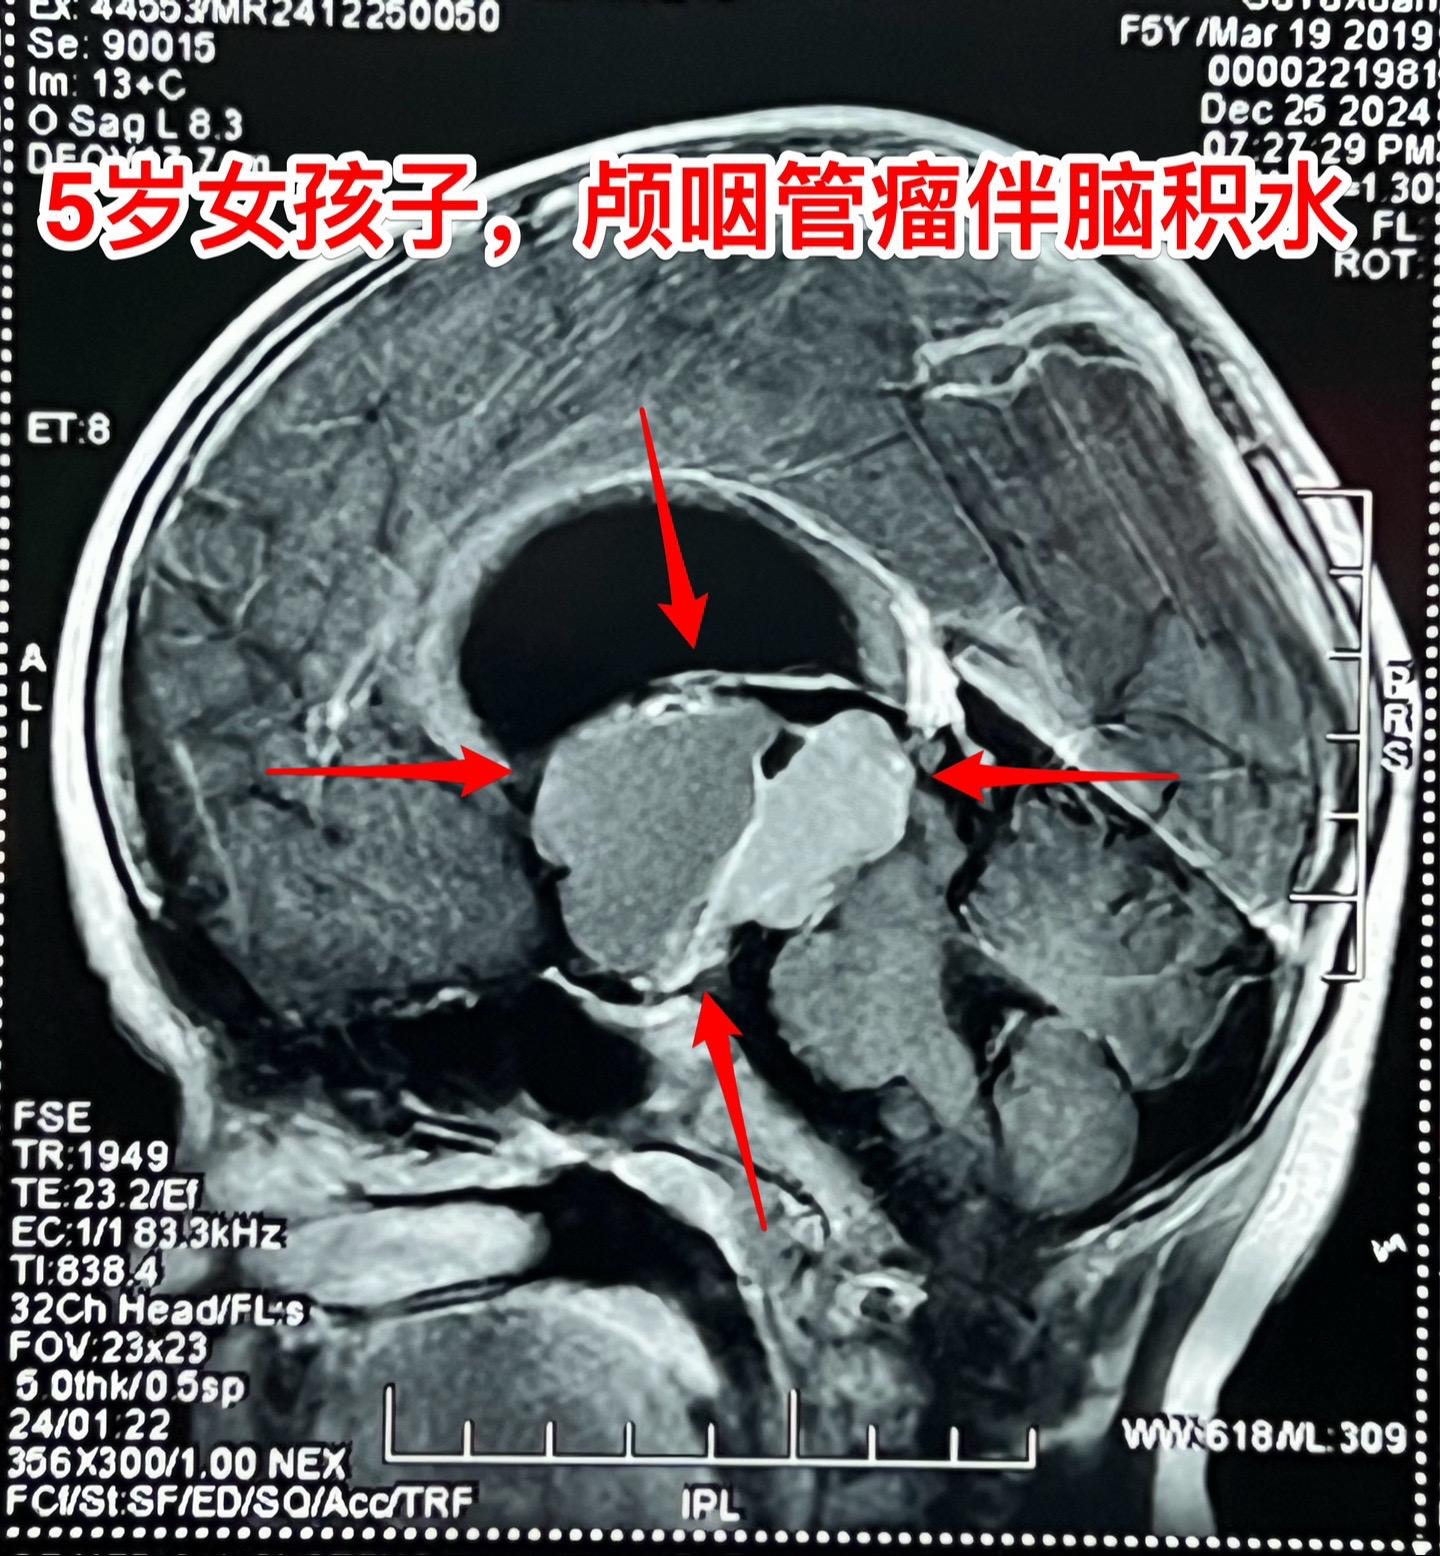

五岁商丘女孩颅咽管瘤像鸡蛋大。女孩子因为反复头痛、呕吐起病,一开始怀疑是胃肠炎,治疗后效果不好。于2024年12月18日作脑部磁共振和CT发现脑部肿瘤,怀疑是颅咽管瘤,孩子的妈妈和我加了,说肿瘤像鸡蛋那么大,焦急万分。 小孩子几经周折,最终到三博脑科医院找我办理住院手续。刚刚住院后又患感冒,发烧、咳嗽。感冒治好之后才于2025月1月7日作了手术。手术很顺利。 这个肿瘤体积大,导致脑积水,主体位于第三脑室内。对于我们科来说,这样的手术还不算是最难的。 希望小